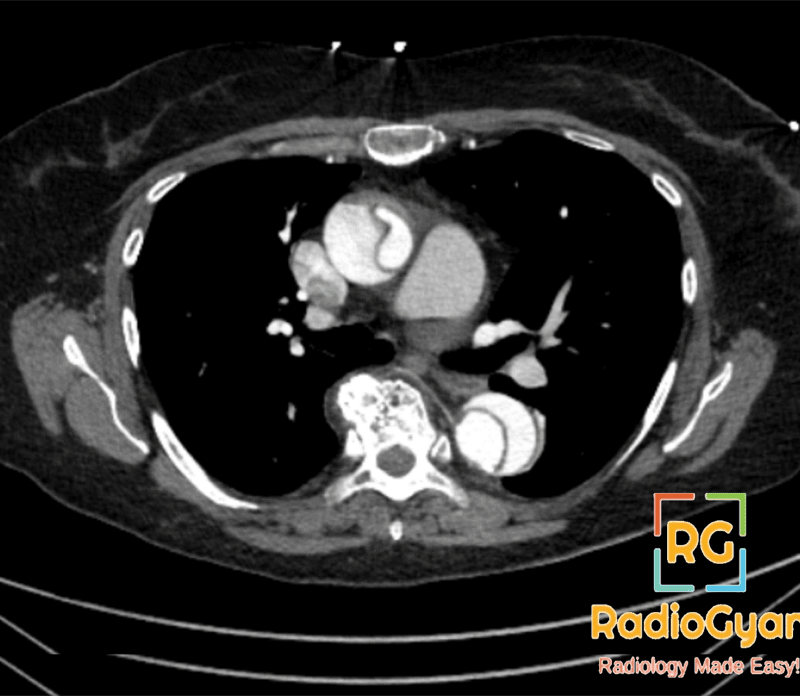

One unique thing about CT scans is the ability to perform a test with and without contrast. Contrast is usually an iodine-based fluid that is taken by IV or mouth to allow a specific organ to appear more defined up on CT scan. This is very helpful in aortic dissections where contrast may help us distinguish between the true and false lumens (true is lighter due to contrast)!